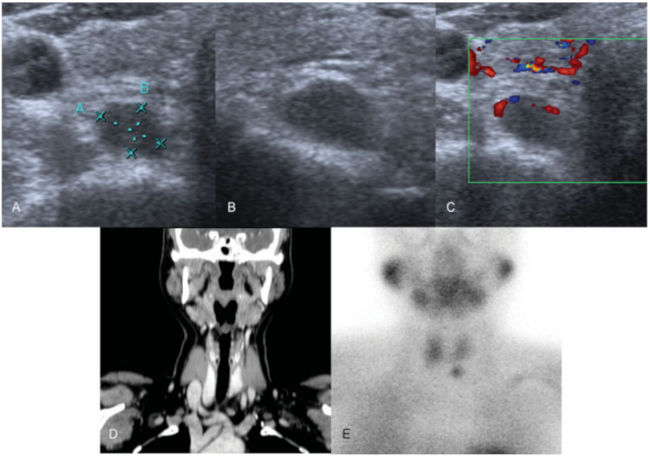

Adenoma de paratiroides en un paciente con MEN tipo 2. En la ecografía imagen transversal (A) y longitudinal (B) se visualizó una lesión redondeada, de contornos bien delimitados e hipoecoica con aporte arterial en su polo superior (C). En la tomografía computada (TC) con contraste intravenoso, corte coronal (D) se objetivó una lesión nodular hipercaptante en localización posterior a la glándula tiroidea.

La gammagrafía con sestamibi, fase precoz (E) muestra una lesión que captó trazador en la misma localización que la imagen b, compatible con adenoma paratiroideo.